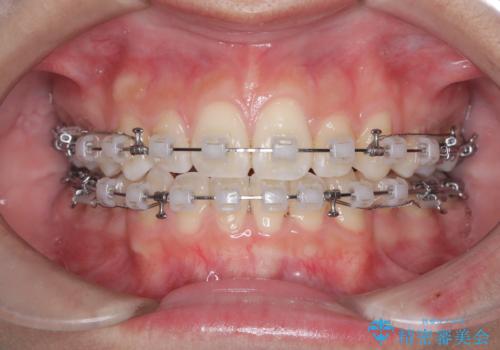

上下左右の第一小臼歯を抜歯し、クリアブラケット(白い装置)とメタルワイヤーを使用して矯正を開始。初期には犬歯のアーチ内への整列を優先し、中盤からは前歯と奥歯の咬合関係の調整を進めました。審美性に優れた装置を使用したことで、治療中も目立ちにくく、見た目へのストレスが少ない点も評価されています。全体の治療は1年半で完了し、見た目・噛み合わせともに大きく改善。患者本人も「短期間でここまで変わるとは思わなかった」と満足されていました。